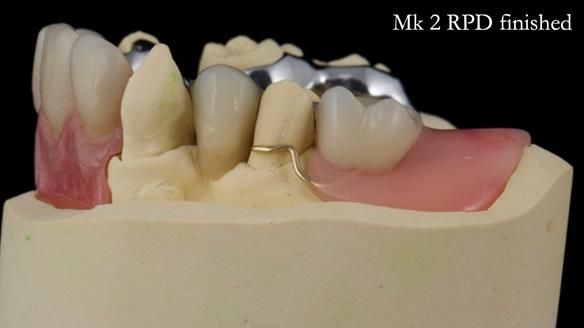

Jean’s Class I Mod III RPD: Learning from My Mistakes – From a Fractured Mk1 to a Stronger Mk2 (4 Years On)

In this edition, I present the removable partial denture treatment for Jean, an 80-year-old woman with a sore mouth caused by a soft tissue-supported 'gum stripper' acrylic denture and a clenching habit. Below, I outline the step-by-step process of her treatment. It wasn't straightforward; I had to remake the denture after it fractured to achieve a satisfactory result. Each patient is unique, and sometimes a new RPD serves as a prototype. Occasionally, I need to make adjustments, learn from any mistakes, and refine the design to get it right.

The treatment has been a success over the past 4 years.